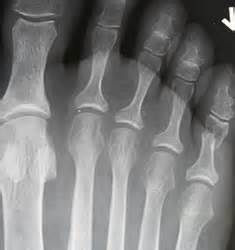

第五腳趾骨折...最常見的腳的腳趾骨折 中壢高正雄骨科復健診所